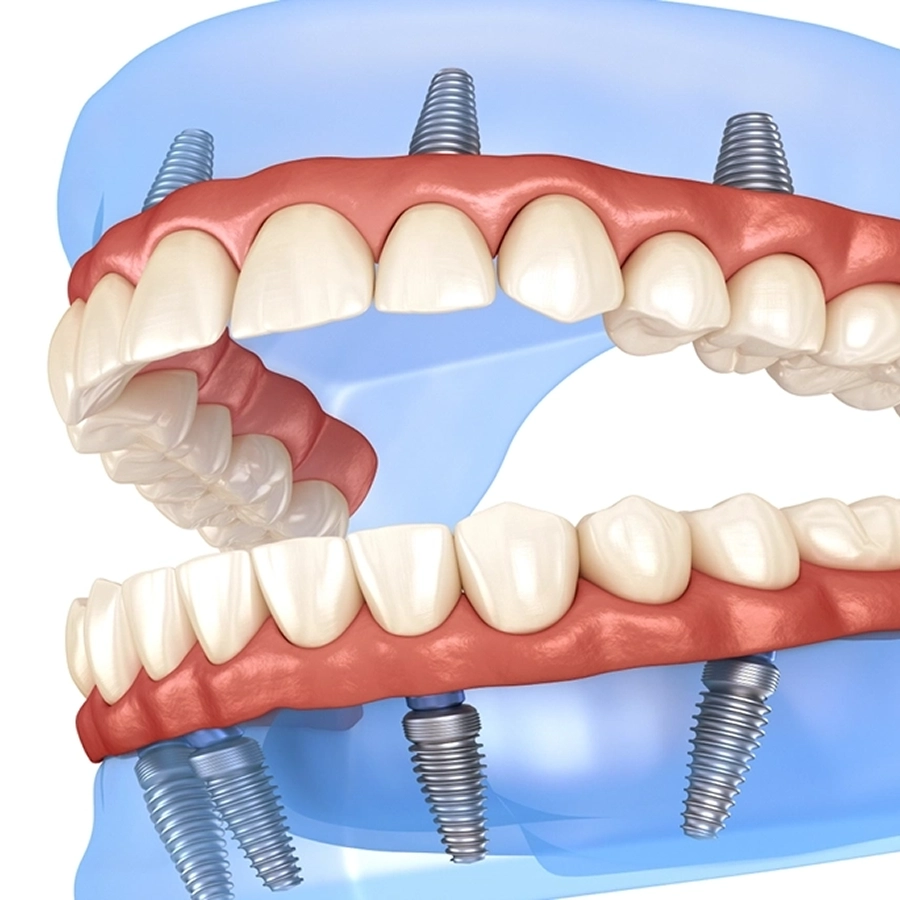

All on X Course Overview

- Place 12 implants

- Restore 3 arches with immediate temporary fixed bridges.

- 3 arches place 4 implants in each arch

- Fully and partially guided surgical placement technique

- Learn to restore immediate fixed prostheses and prosthodontic considerations.

What does the All‑on‑X Course include?

The All‑on‑X Course is a week‑long live patient programme held at the University of Chennai, India. Participants typically place 12 implants and restore up to three full arches with immediate fixed provisional bridges. The learning includes CBCT‑based diagnosis and planning plus fully or partially guided implant placement, surgical suturing, prosthetic workflows and treatment from start to finish with specialist mentor support.